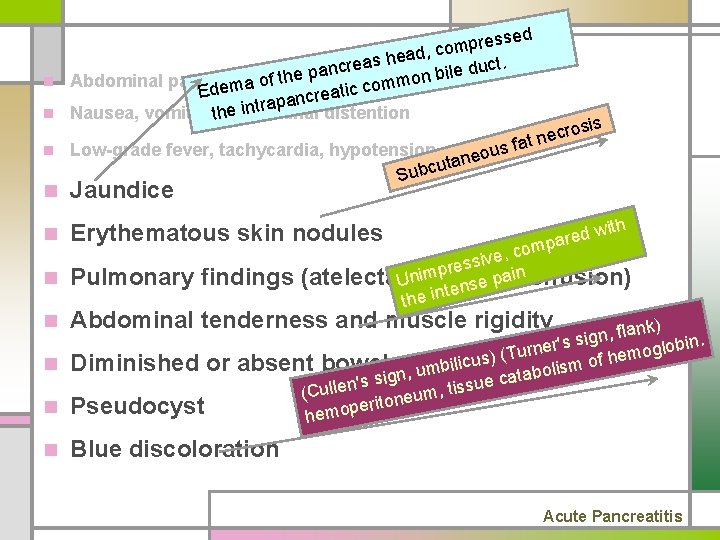

n Abdominal pain n Nausea, vomiting, abdominal distention n Low-grade fever, tachycardia, hypotension, shock n Jaundice n Erythematous skin nodules n Pulmonary findings (atelectasis, pleural effusion) n Abdominal tenderness and muscle rigidity n Diminished or absent bowel sounds n Pseudocyst n Blue discoloration Acute Pancreatitis

ssed e r p m o ead, c h s a e r duct. nc a e l i p b e n h t n Abdominal pain of ommo c c i t Edema a ancre p a r t n i n Nausea, vomiting, theabdominal distention osis r c e fat n s n Low-grade fever, tachycardia, hypotension, shock u o ne a t u c Sub n Jaundice n Erythematous skin nodules n Pulmonary findings n Abdominal tenderness and muscle rigidity n Diminished or n Pseudocyst n Blue discoloration ed w r a p m ith , co e v i s res p m i ain effusion) n (atelectasis, pleural p U e s ten the in nk) a l f , n g r's si bin. e o l n g r o u T f hem us) ( o c i l i absent bowelgsounds m b s i l m n, u tabo a i c s s e ' u n s , tis (Culle m u e n o erit hemop Acute Pancreatitis